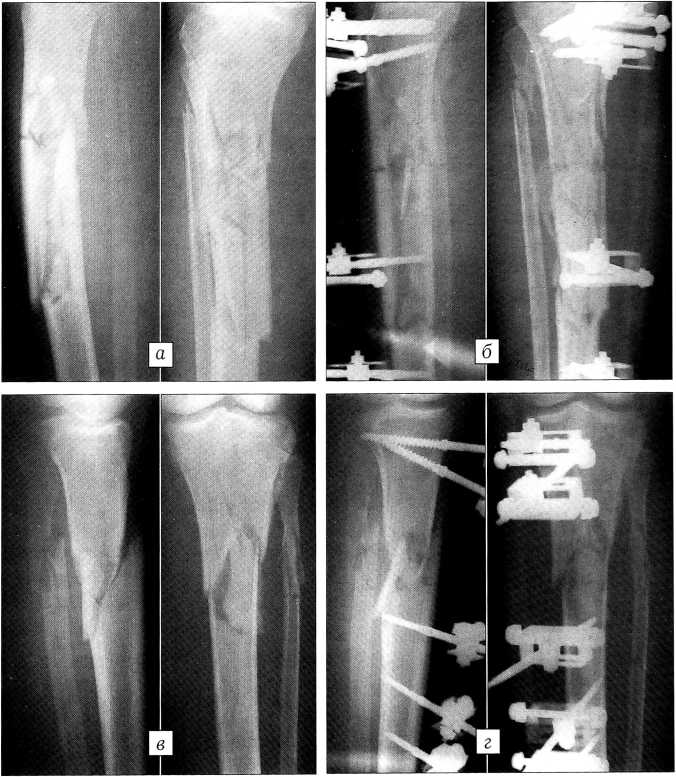

Рис. 2. Рентгенограммы больного С.: а — при поступлении, б — после остеосинтеза.

Больной Д . ,39 лет, доставлен в стационар через 5 ч после получения травмы (сбит автомашиной при переходе улицы). По результатам клинического и рентгенологического обследования диагностированы открытые оскольчатые переломы диафиза костей обеих голеней со смещением отломков типа С1 (рис. 3, а, в); травматический шок II степени. В день поступления произведен остеосинтез переломов обеих голеней стержневыми аппаратами с «плавающими» фиксаторами стержней (рис. 3, б, г). Через проколы кожи и мягких тканей длиной до 1 см по внутренней поверхности голеней введено по три стержня в проксимальный и дистальный отломки. После стабилизации проксимальных стержней в аппаратах выполнены закрытая репозиция с помощью съемных рукояток и фиксация дистальных стержней.

Рис. 3. Рентгенограммы больного Д.: а — правая голень при поступлении, б — после операции; в — левая голень при поступлении, г — после операции.

Пациент выписан на амбулаторное лечение через 15 дней. К этому времени ходил без дополнительных средств опоры, объем движений при сгибании в левом коленном суставе составлял 0-100°, в правом — 0-120° (рис. 4, а). После сращения перелома и демонтажа аппаратов объем движений в обоих коленных суставах восстановлен полностью (рис. 4, б).